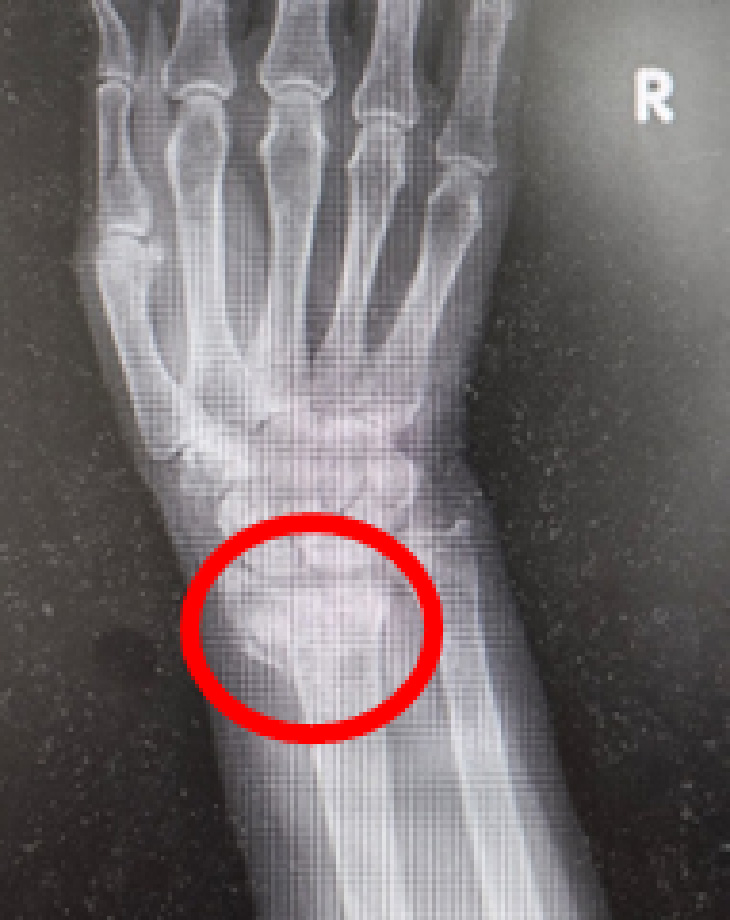

橈骨遠位端骨折

骨を治すだけでなく、“動きを取り戻す”治療

橈骨遠位端骨折とは

橈骨遠位端骨折は、手首の骨(橈骨)の先端部分が折れる骨折です。

転倒して手をついたときに多く発生し、特に中高年の女性や骨粗しょう症のある方に多く見られます。

見た目は軽い捻挫のようでも、実際には骨折していることがあり、適切な治療を行わないと手首の変形や可動域の制限が残る場合があります。

早期の診断と治療が大切です。

主な症状

・手首の腫れや強い痛み

・手首を動かせない、物を持てない

・手首の変形(手の甲が盛り上がって見える)

・押すと強く痛む部位がある

・指先のしびれや感覚の鈍さ